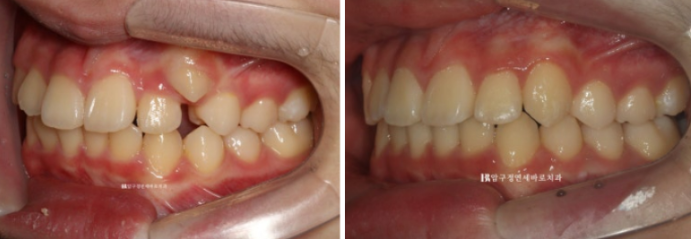

처음과 끝

덧니가 온전히 제자리를 찾았습니다.